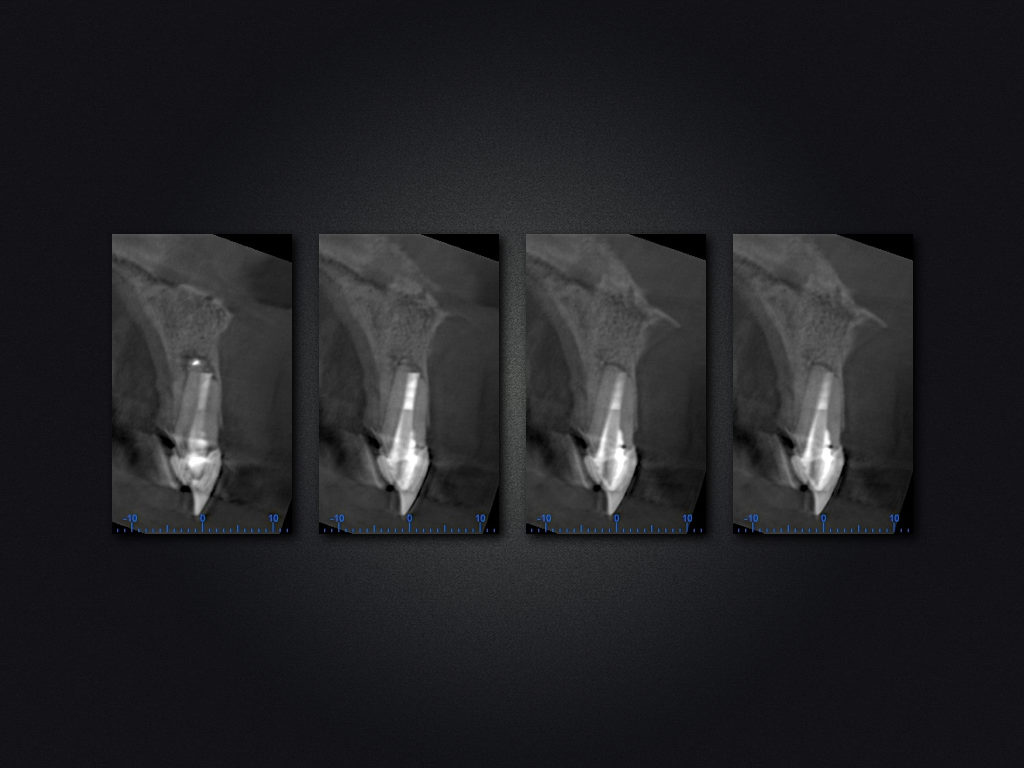

11D.013

Und es heilt doch!